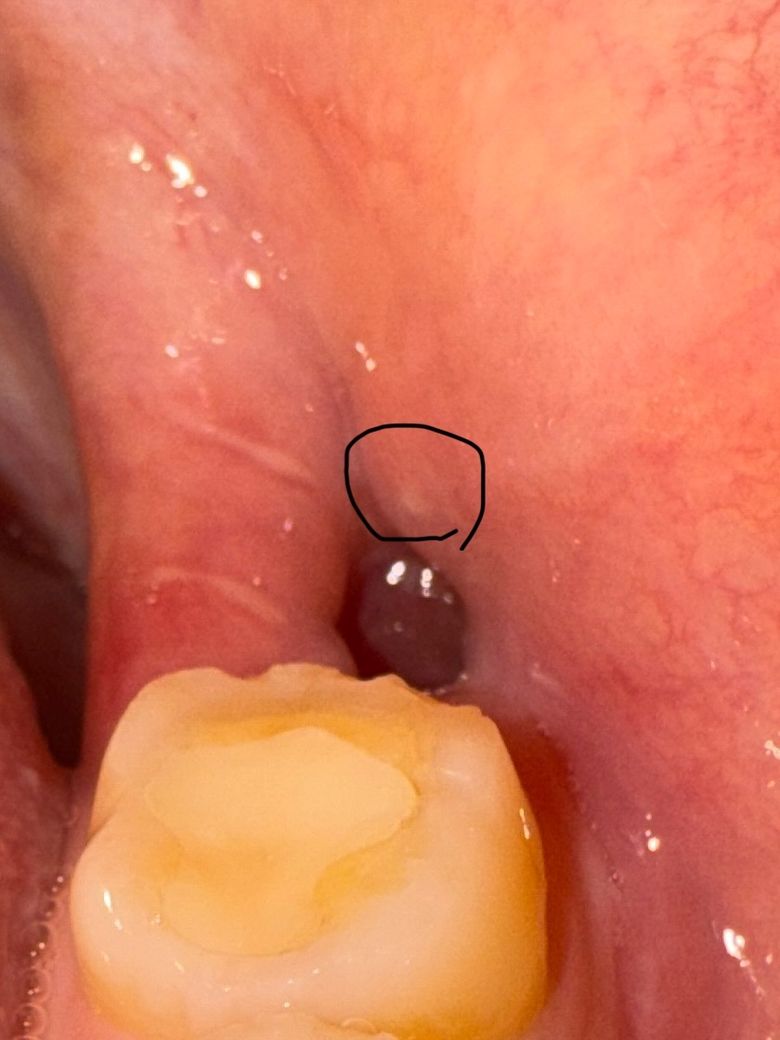

사랑니 발치후 구멍 옆에 염증인가요?ㅜㅜ +물주사기 사용

매복 사랑니 발치한지 10일됐는데 구멍이 뚫려있고 그 옆에 손으로 만지면 살짝 딱딱하게 튀어나온게 있는데 염증인가요? ㅜㅜ 누르면 아파요....

그리고 양치하기 전까지만 해도 구멍에 하얀색으로 뭐가 껴있었는데 물 주사기로 빼내니 싹 다 빠지고 구멍만 남았거든요.. 음식물을 뺀게 맞겠죠? 아니면 혈병일수도 있나요? 드라이소켓 걸리는건가요 ㅠㅜㅜㅜ 앞으로 물주사기 사용 안하는게 낫나요?

• 1번 째 사진